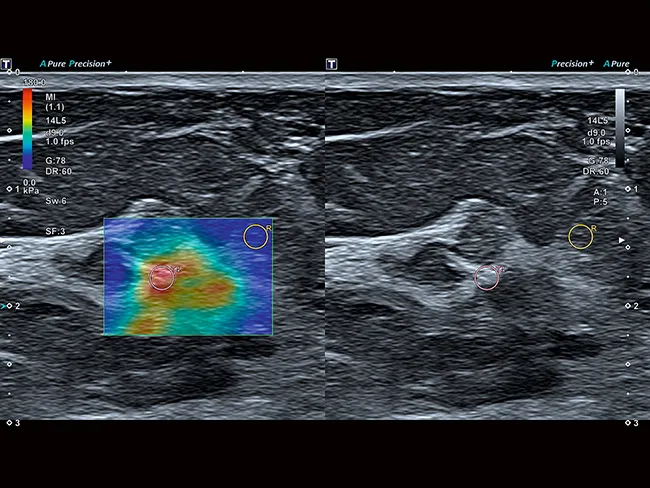

Комплексная система тензоэластографии с функциональными возможностями обработки исходных данных помогает вам локализовать и оценить пальпируемые образования с высокой точностью, чувствительностью и воспроизводимостью.